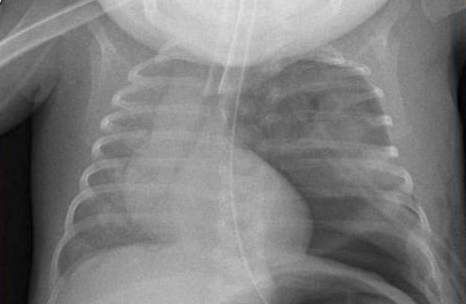

Catheter Ombilical Arteriel et Veineux

Sonde Trachéale et Drain Pleural

SNG

chest tubes lines line ligne lignes line vvc voies veineuses catheter cathéter ombilic ombilical ombilicales